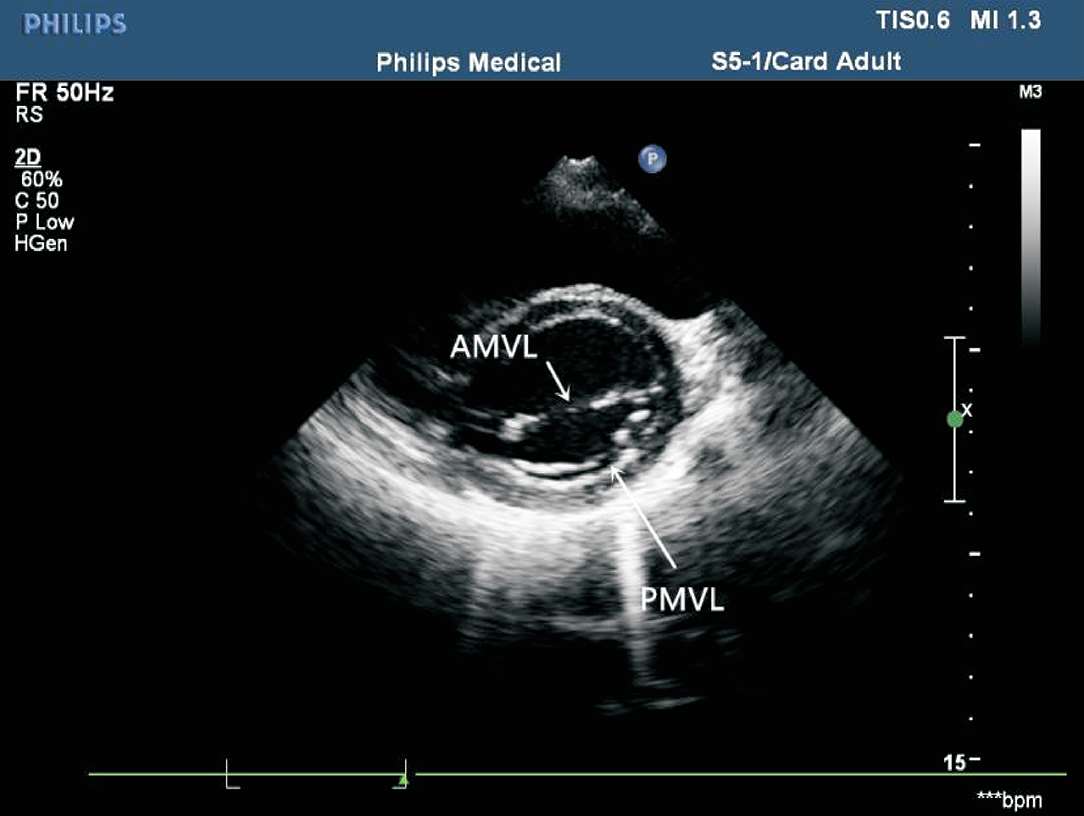

患者取左侧卧位或平卧位,探头置于胸骨左缘第3~4 肋间,声束垂直于胸骨旁左心室长轴切面,斜向后方扫查。在此切面可观察二尖瓣前后叶的形态及开放程度,肌部室间隔的完整性,心室壁基底段的厚度、回声强度及有无节段性运动异常(见图1-29)。

图1-29 二尖瓣水平左心室短轴切面(AMVL:二尖瓣前叶;PMVL:二尖瓣后叶)